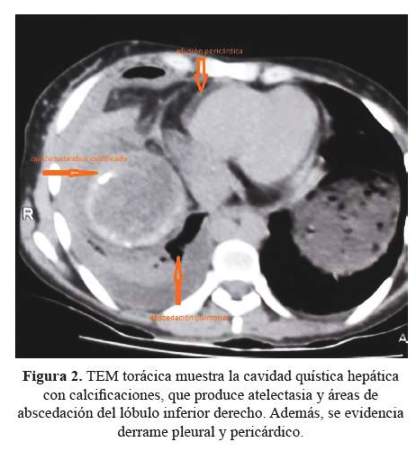

La tomografía espiral multicorte (TEM) abdomino torácica mostró una tumoración quística bilobulada en la base de hemitórax y región subfrénica del lado derecho; además, un quiste hidatídico hepático con comunicación a la cavidad pleural (figura 1), un área de condensación con zona de abscedación comprometiendo el lóbulo medio, atelectasia pasiva del lóbulo inferior derecho y moderado derrame pleural (figura 2).

El ecocardiograma mostró cavidades normales; motilidad regional y global del VI conservada; FEVI 63%; función sistólica del VD conservada TAPSE <18mm, derrame pericárdico a predominio de pared posterior de 210 ml aproximadamente, sin signos de taponamiento y abundante fibrina.